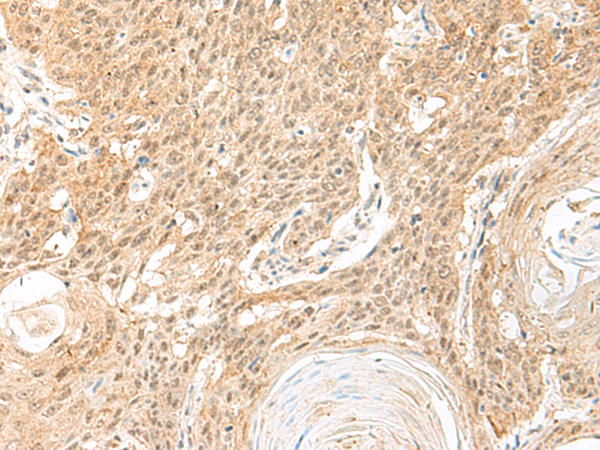

分类: 科研抗体货号: P13465别名: GA; GLS; LGA; hLGA应用: WB,IHC反应种属: Human, Mouse, Rat

鄂公网安备42018502007531号